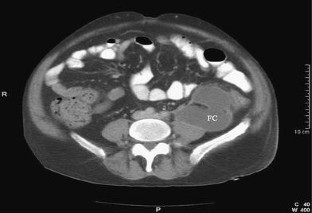

Unusual presentation of acute pancreatitis: an irreducible inguinoscrotal swelling mimicking a strangulated hernia

We report an unusual presentation of acute pancreatitis as a tender, irreducible, inguinoscrotal swelling mimicking a strangulated hernia. Lack of abdominal symptoms or signs can lead to misdiagnosis and unnecessary surgery.

Fig. 2.